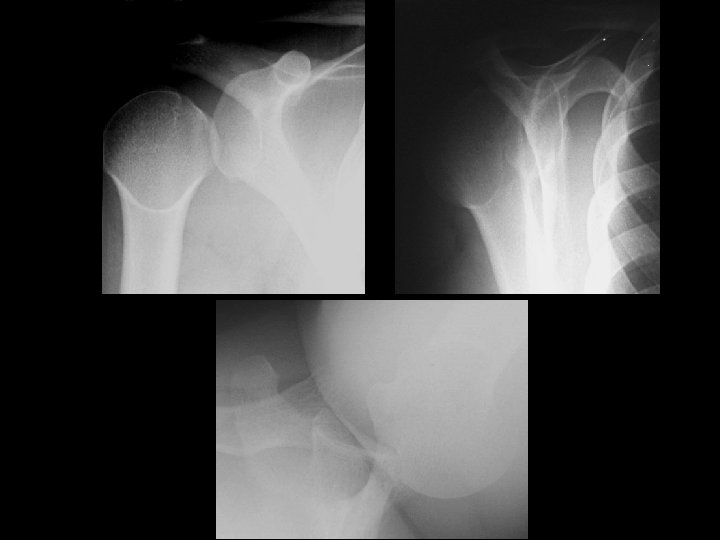

Anterior shoulder dislocation • Findings: – Inferomedial subcoracoid displacement of the humeral head – Too much overlap of humeral head and bony glenoid – Axillary view is diagnositic and shows Hill-Sachs and Bankhart lesions • ddx: – NONE! – This is an Aunt Minnie!

Posterior shoulder dislocation • Findings: – Lateral displacement of the humeral head – “Empty glenoid sign” – Axiallary and transscapular Y views are diagnostic – “Trough sign” and posterior bony glenoid impaction • ddx: – NONE! – This is an Aunt Minnie!